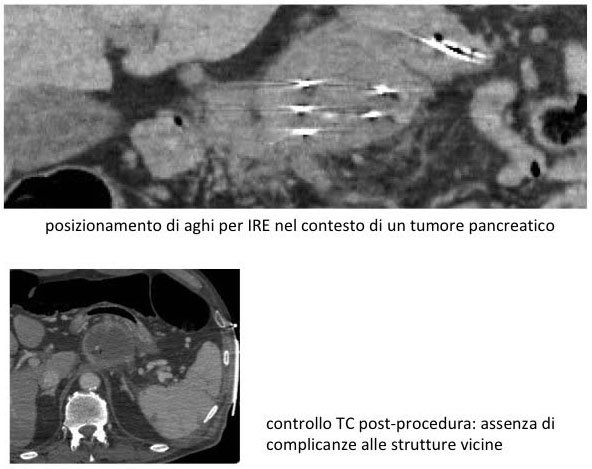

Per guidare l’inserzione ed il posizionamento degli aghi nel tumore come in qualsiasi

altra procedura di radiologia interventistica, si usa l’ecografia o la TC o la CBCT,

o due di queste metodiche in combinazione.